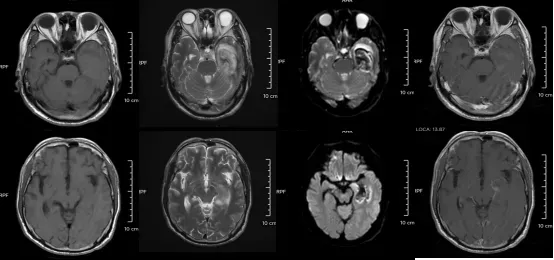

脑部磁共振报告显示其“双侧额颞部脑膜稍增厚伴强化”,提示脑膜炎。经5天抗病毒治疗,小李病情好转出院。

送医途中,小张病情急剧恶化,转至宁波大学附属第一医院时已陷入昏迷。经检查,小张确诊“病毒性脑膜炎伴脑炎”,这意味着他不仅脑膜发炎,脑实质也受到感染。